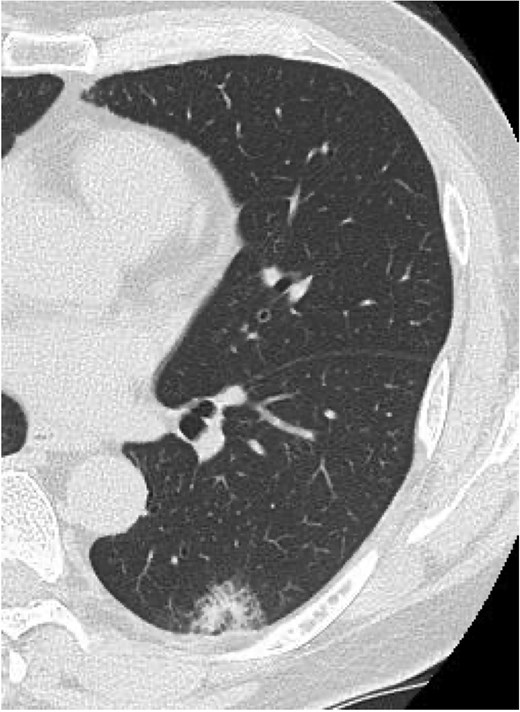

On POD 10, he developed fever and tested positive for COVID-19 by reverse transcription-polymerase chain reaction. Nosocomial transmission was suspected given recent ward cases during the delta variant outbreak. Chest computed tomography showed minimal peripheral ground-glass opacities in the right upper lobe (Fig. 2a and b). He received remdesivir (5 days) and dexamethasone (7 days), maintained adequate oxygenation without supplemental oxygen, and was discharged on POD 21 after clinical improvement.

Serial chest imaging demonstrating pulmonary complications. (a) Postoperative day (POD) 10: Initial presentation without significant abnormalities. (b) POD 16: Peripheral ground-glass opacities (arrowheads). (c) POD 27: Patchy consolidation (solid arrows) with new ground-glass opacities and pleural effusion (open arrows). (d) POD 36: Progressive consolidation (solid arrows).